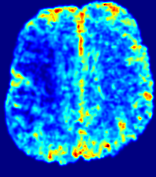

LesionRefer to captionRefer to captionRefer to captionRefer to captionRefer to captionRefer to caption𝐕rgbsubscript𝐕𝑟𝑔𝑏{\bf{V}}_{rgb}Refer to captionRefer to captionRefer to captionRefer to captionRefer to captionRefer to caption𝐕2subscriptnorm𝐕2{\|\bf{V}}\|_{2}Refer to captionRefer to captionRefer to captionRefer to captionRefer to captionRefer to captionRefer to caption3.53.53.52.82.82.82.12.12.11.41.41.40.70.70.70.00.00.0(mm/s)𝑚𝑚𝑠(mm/s)D𝐷DRefer to captionRefer to captionRefer to captionRefer to captionRefer to captionRefer to captionRefer to caption0.0200.0200.0200.0160.0160.0160.0120.0120.0120.0080.0080.0080.0040.0040.0040.0000.0000.000(mm2/s)𝑚superscript𝑚2𝑠(mm^{2}/s)Slice #1Slice #2Slice #3Slice #4Slice #5Slice #6

Figure 3: PIANO feature maps for one stroke patient, where the lesion is located in the left hemisphere. Top row: segmented stroke lesion region (white) on different slices, obtained from ISLES 2017. The corresponding slices for the PIANO feature maps are shown in the following rows.

For a better insight into an estimated velocity field 𝐕𝐕{\bf{V}} and diffusion field 𝐃𝐃{\bf{D}}, we compute the following maps: (1) 𝐕rgbsubscript𝐕𝑟𝑔𝑏{\bf{V}}_{rgb}: Color-coded orientation map of 𝐕=(Vx,Vy,Vz)T𝐕superscriptsuperscript𝑉𝑥superscript𝑉𝑦superscript𝑉𝑧𝑇{\bf{V}}=(V^{x},V^{y},V^{z})^{T}, obtained by normalizing 𝐕𝐕{\bf{V}} to unit length and mapping its 3 components to red, green, blue respectively; (2) 𝐕2subscriptnorm𝐕2\|{\bf{V}}\|_{2}: 222 norm of 𝐕𝐕{\bf{V}}; (3) D𝐷D: scalar field in Eq. 5.

Fig. 3 and Fig. 4 show the PIANO feature maps estimated from two ISLES 2017 patients: all are highly consistent with the lesion in both cases. Details of the blood flow trajectories are revealed in 𝐕rgbsubscript𝐕𝑟𝑔𝑏{\bf{V}}_{rgb} by the ridged patterns and the sharp changes of colors in the unaffected (right) hemisphere, while the flat patterns appearing within the lesion provide little directional information about the velocity and indicate low velocity magnitudes. Velocity magnitudes are more directly visualized via 𝐕2subscriptnorm𝐕2\|{\bf{V}}\|_{2}, from which one can easily locate the lesion where 𝐕2subscriptnorm𝐕2\|{\bf{V}}\|_{2} is low. D𝐷D also indicates lower diffusion values in the lesion, though with less contrast potentially due to the fact that it captures the accumulated effect of CA diffusion at the voxel-level.